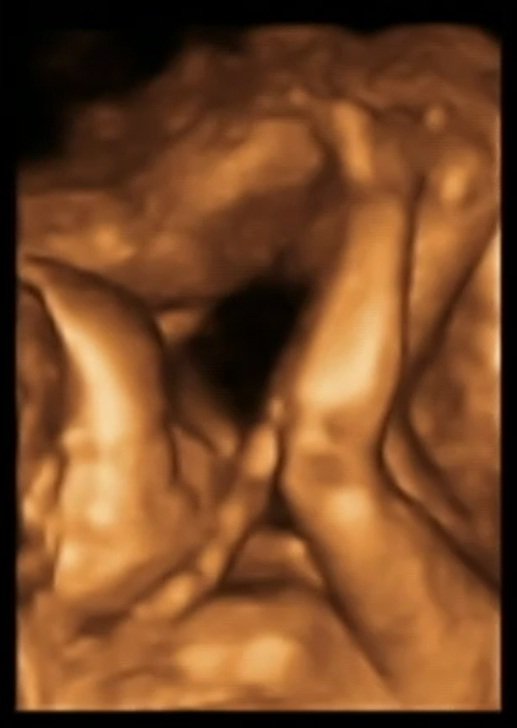

A więc moje kochane będziemy mieli córeczkę [emoji7] moja śliczna księżniczka jest zdrowa jak ryba i waży 340g. Ogólnie wszystko jest prawidłowo i cacy [emoji7] jestem najszczęśliwsza mama na świecie !

A oto ona i jej słodkie nóżki [emoji173]️[emoji171][emoji169][emoji172]